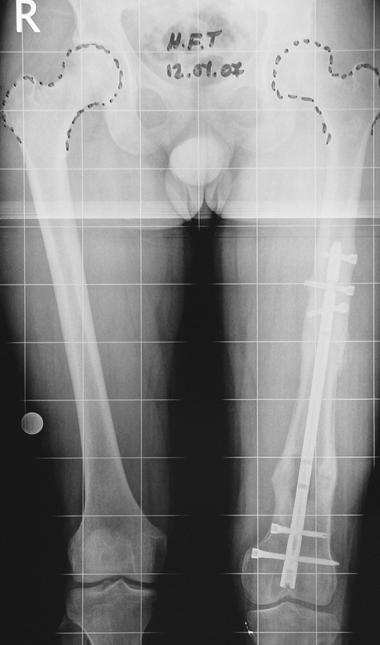

3. POSTTRAUMATIC LOWER LIMB SHORTNESS (MALUNION)

This type of shortness occurs after a fracture heals in a shortened position. Most cases are seen in adults and can be treated with one lengthening operation. Additional deformities can be corrected simultaneously. Most of these cases can be treated with lengthening over nail or just corrections and intramedullary nailing.